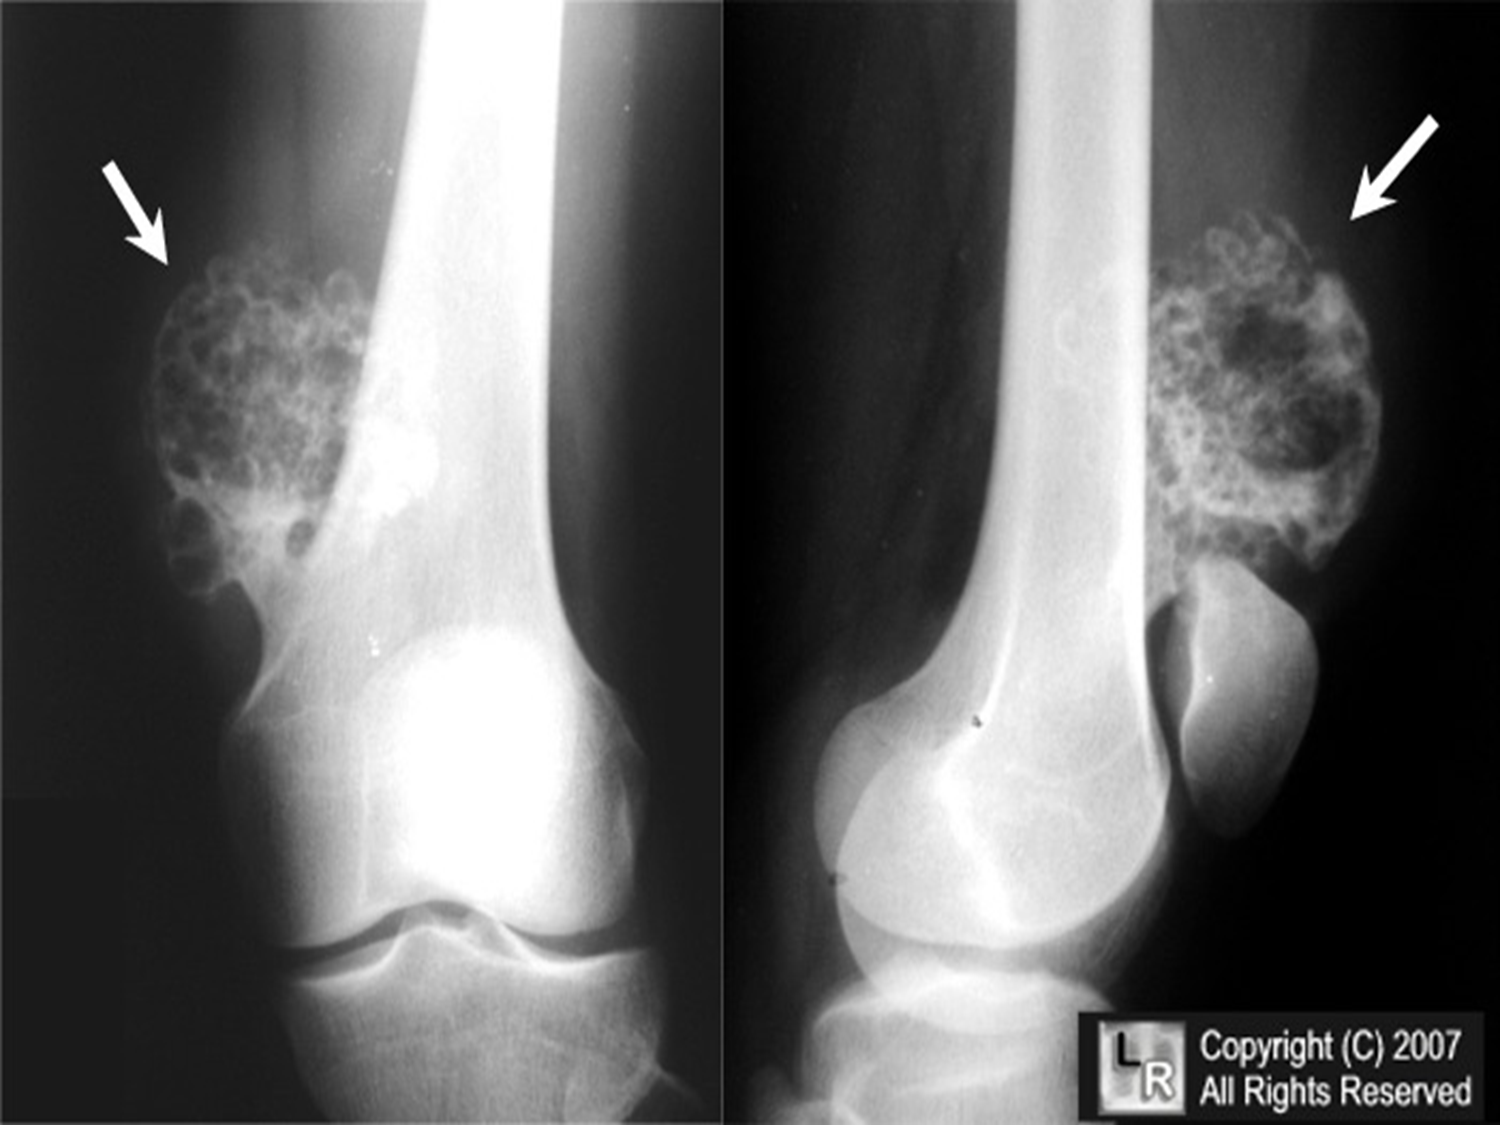

osteochondroma (exostosis)

benign projection of bone w/ a cartilaginous cap

idiopathic, hereditary

what is the cause of osteochondroma?

pt w/ osteochondroma

what is this image?